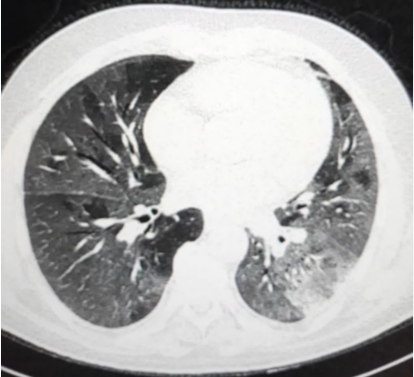

Figura 5 Imazhe CT të pulmonit të prekur nga Covid-19.

Gjatë periudhës së pandemisë së COVID-19 numri i ekzaminimeve imazherike, si radiografia dhe CT e pulmonit janë rritur ndjeshëm për qëllime të diagnostike, te prekjes pulmonare nga virusi SARS-Cov-2. Sipas rekomandimeve të Organizatës Botërore të Shëndetësisë, RT-PCR (tamponi) duhet të përdoret për të konfirmuar diagnozën e Covid-19 (përjashto rastet e procedurave emergjente intervencionuese kur RT-PCR nuk është në dispozcion ose rezultatet vonojnë).

Figura 3. Iustrim ekzaminimi skanimi CT

Shumica e shoqërive mjekësore shprehen kundër përdorimit rutinë të teknikave imazherike për diagnozën e rasteve të dyshuara për Covid-19. Ato rekomandojnë përdorimin e ekzaminimeve imazherike për pulmonin vetëm në rastet e pacientëve të konfirmuar pozitiv për Covid-19 (bazuar në të dhënat e testeve laboratorike) dhe përbërës klinik në të cilët dyshohet për progresion të sëmundjes dhe komplikacione si pneumoni, tromboemboli pulmonare etj.